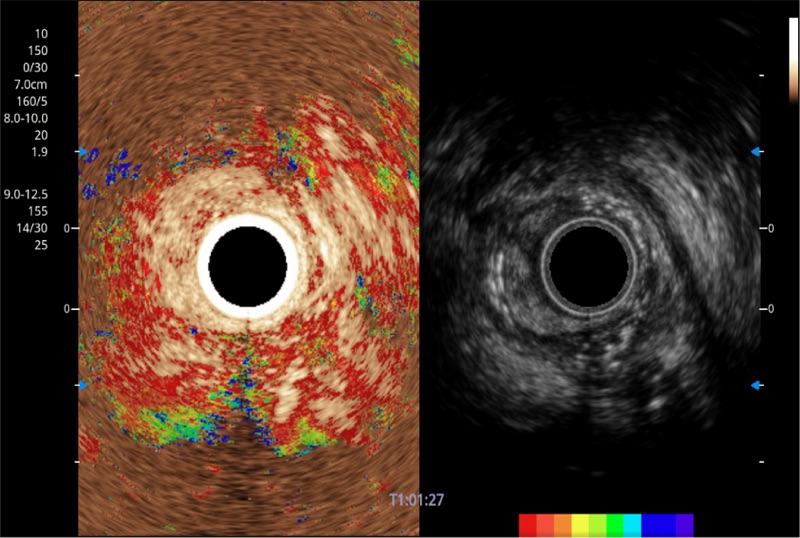

• 弹性成像

位移矫正技术

不可靠区域自动剔除

弹性定量分析软件